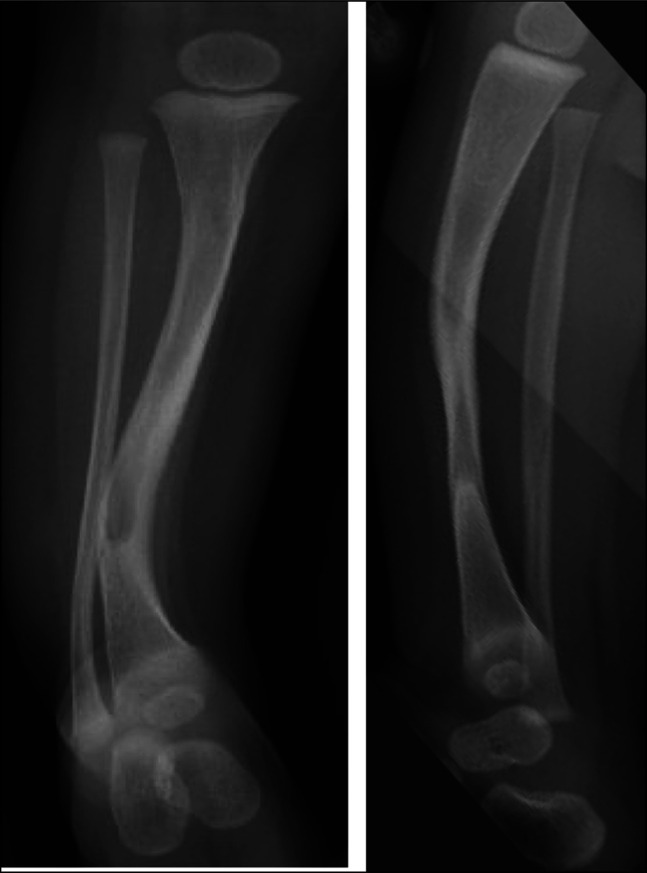

1型神经纤维瘤病(NF-1)导致皮肤、神经和肌肉骨骼表现。先天性胫骨假关节治疗被认为是实现骨愈合的积极手段。大多数患者在治疗结束时由于病理性骨切除和不对齐而导致肢体短。患者可能出现的表现之一是肢体局部半肥厚。在我们的病例中,我们首次报道了同一条腿先天性胫骨假关节和半肥厚并存的情况。

Neurofibromatosis type 1 (NF-1) leads to cutaneous, neurological, and musculoskeletal manifestations. Congenital pseudarthrosis of the tibia treatment is considered aggressive in achieving bone union. Most of those patients get a short limb at the end of treatment because of pathological bone resection and malalignment. One of the manifestations that can appear in patients is localized hemihypertrophy of the limb. In our case, we present the first time a coexistence of congenital pseudarthrosis of the tibia and hemihypertrophy in the same leg was reported.